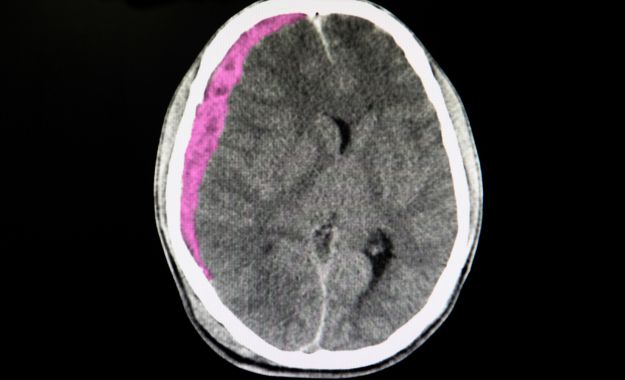

hematome sous dural

L'hématome sous-dural représente la complication la plus fréquente et la plus redoutable chez les seniors. Cette accumulation de sang entre le cerveau et la dure-mère peut se développer lentement, sur plusieurs jours ou semaines. Chez les personnes âgées, même un choc mineur peut provoquer cette lésion en raison de la fragilité accrue des vaisseaux sanguins et de l'atrophie cérébrale naturelle qui crée un espace plus important dans la boîte crânienne. Les symptômes peuvent inclure des maux de tête persistants, une somnolence progressive, des troubles de la mémoire ou des changements de comportement.